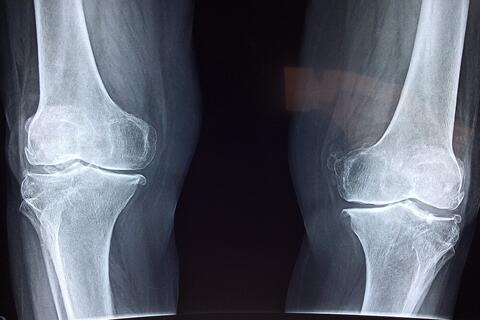

به گزارش مشرق، دکتر سید مهدی میرغضنفری - معاون تعالی دفتر طب ایرانی و مکمل وزارت بهداشت با اشاره به شیوع پوکی استخوان خصوصا در سنین بالا، نگاه طب ایرانی به این بیماری را تشریح کرد و گفت: از دیدگاه مشترک طب ایرانی و فیزیولوژی مدرن، استخوان یک بافت زنده و پویا است که همواره در حال تخریب و بازسازی است و برای حفظ سلامت آن، ضروری است که از طریق جریان خون، غذای باکیفیت و مناسبی دریافت کند.

وی تاکید کرد: اگر خون کیفیت لازم را نداشته باشد، تغذیه مناسبی برای استخوان صورت نمی‌گیرد و مواد ضروری برای رشد و بازسازی به آن نمی‌رسد. در نتیجه استخوان به‌تدریج ضعیف‌تر می‌شود که به این حالت اصطلاحاً پوکی استخوان گفته می‌شود.